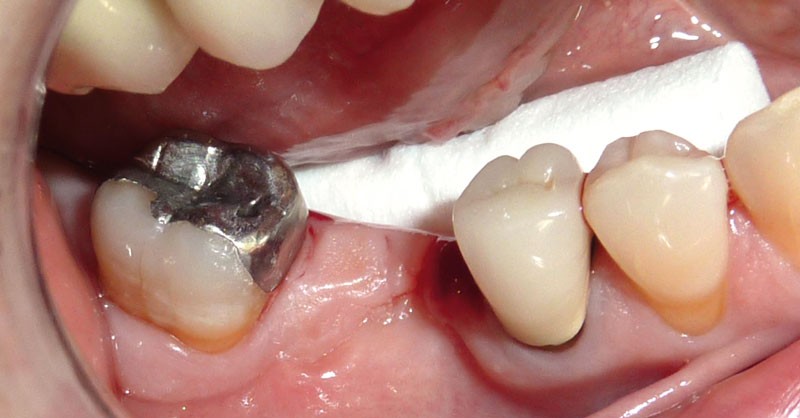

Un patient se présente pour le descellement d’un bridge 45-47 au niveau de l’onlay en 47 (fig. 1).

Afin de préserver la 45, il lui est proposé de couper le bridge en distal de 45 et en mésial de 47, de resceller l’onlay sur 47 et de poser un implant au niveau de 46, cela afin d’éviter un inévitable redescellement de la prothèse (fig. 2).

La perte osseuse vestibulaire dans ce secteur (fig. 3) ainsi…